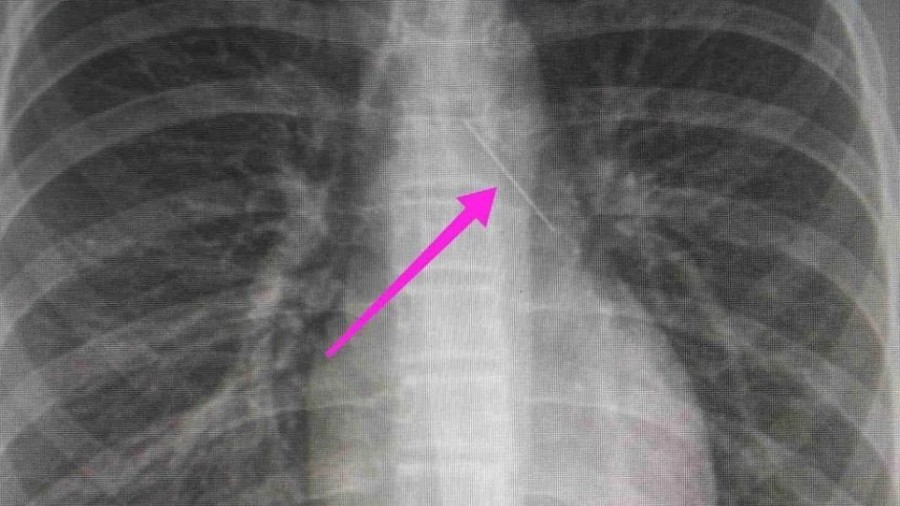

Από την απεικονιστική διερεύνηση που πραγματοποιήθηκε με ακτινογραφία θώρακος αρχικά και ακολούθως με αξονική τομογραφία θώρακος, διαπιστώθηκε η ύπαρξη αιχμηρού μεταλλικού ξένου σώματος στην αναπνευστική οδό (δεξιός κύριος βρόγχος) και όχι στην πεπτική οδό, αναφέρει η ανακοίνωση του νοσοκομείου, στα μέσα κοινωνικής δικτύωσης.

“Χθες 30/1/2022 στις 16:00 στο Τ.Ε.Π. του ΓΝΘ Ιπποκράτειο, προσήλθε ανήλικη συνοδευόμενη από τους γονείς της, μετά από αναφερόμενη κατάποση ξένου σώματος (καρφίτσα). Από την απεικονιστική διερεύνηση που πραγματοποιήθηκε με ακτινογραφία θώρακος αρχικά και ακολούθως με αξονική τομογραφία θώρακος, διαπιστώθηκε η ύπαρξη αιχμηρού μεταλλικού ξένου σώματος στην αναπνευστική οδό (αριστερός κύριος βρόγχος) και όχι στην πεπτική οδό.